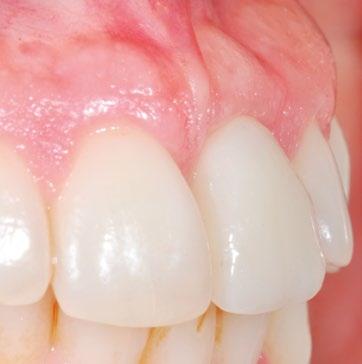

Tras 4 meses (Fig. 20, 21), se inicia la fase final de acondicionamiento mediante adición de composite a la corona provisional, presionando sobre el tejido ya maduro hasta modelar la emergencia simétrica a su contralateral, durante 2 meses más (Fig. 22).

Este abordaje permite conseguir una estabilidad del implante y de los tejidos duros y blandos, y un resultado estético óptimo (Fig. 25, 26, 27, 28). 